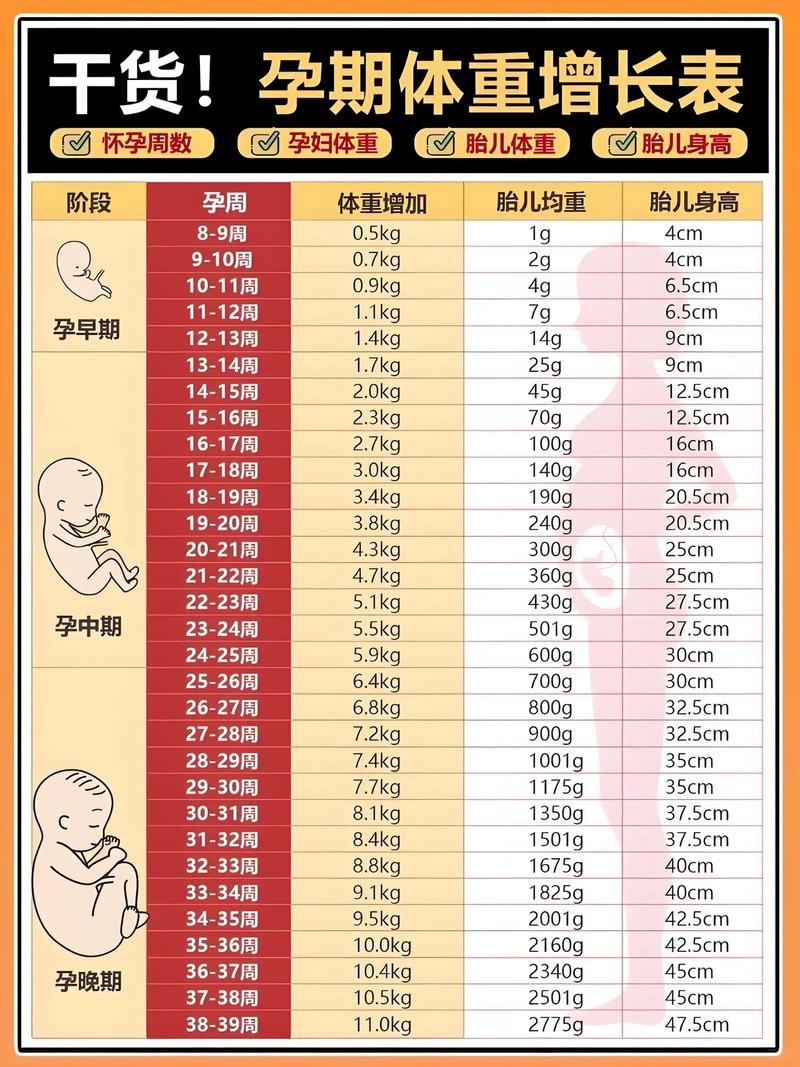

回到最初的问题:孕期增长16斤,到底正不正常?

答案是:对于部分准妈妈来说,16斤是一个非常理想甚至“完美”的增重数字;但对于另一些人来说,则可能意味着体重增长不足。 关键不在于数字本身,而在于增长数字背后的“起点”——你的孕前体重。

我们再来审视“孕期增长16斤”这个数字:

- 如果你的孕前BMI在正常范围(18.5-23.9): 恭喜你!16斤的增重完美地落在了14-22斤的推荐区间内,这不仅不会增加你和宝宝的风险,甚至可以说是“神仙体重”,说明你的孕期营养管理做得非常到位。

- 如果你的孕前BMI偏低(<18.5): 16斤的增重可能略低于下限(22斤),虽然不一定有问题,但需要警惕是否存在营养摄入不足的情况,可能需要适当增加优质蛋白质和健康脂肪的摄入。

- 如果你的孕前BMI已经超重或肥胖(≥24.0): 那么16斤的增重对于你来说可能已经超出了推荐范围,超重或肥胖的准妈妈孕期增重过多,会显著增加妊娠期糖尿病、高血压、巨大儿、剖宫产以及产后难以恢复体型的风险。

16斤本身不是一个绝对的标准,把它放到你的孕前BMI背景下,它的意义才真正显现。

现在你应该有了清晰的答案:对于孕前体重正常的你,16斤是“黄金数字”;对于体重过轻的你,它可能略低;而对于体重超重的你,它可能过高。

孕期体重管理的核心,不是追求一个孤立的数字,而是追求一个健康的增长过程,它关乎你自己的健康,更关乎宝宝一生的起点。